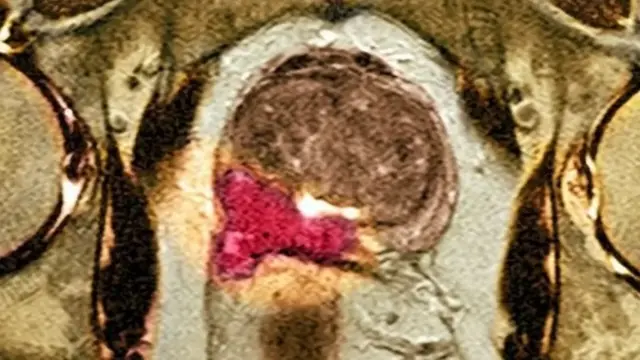

Kaynak, SPL